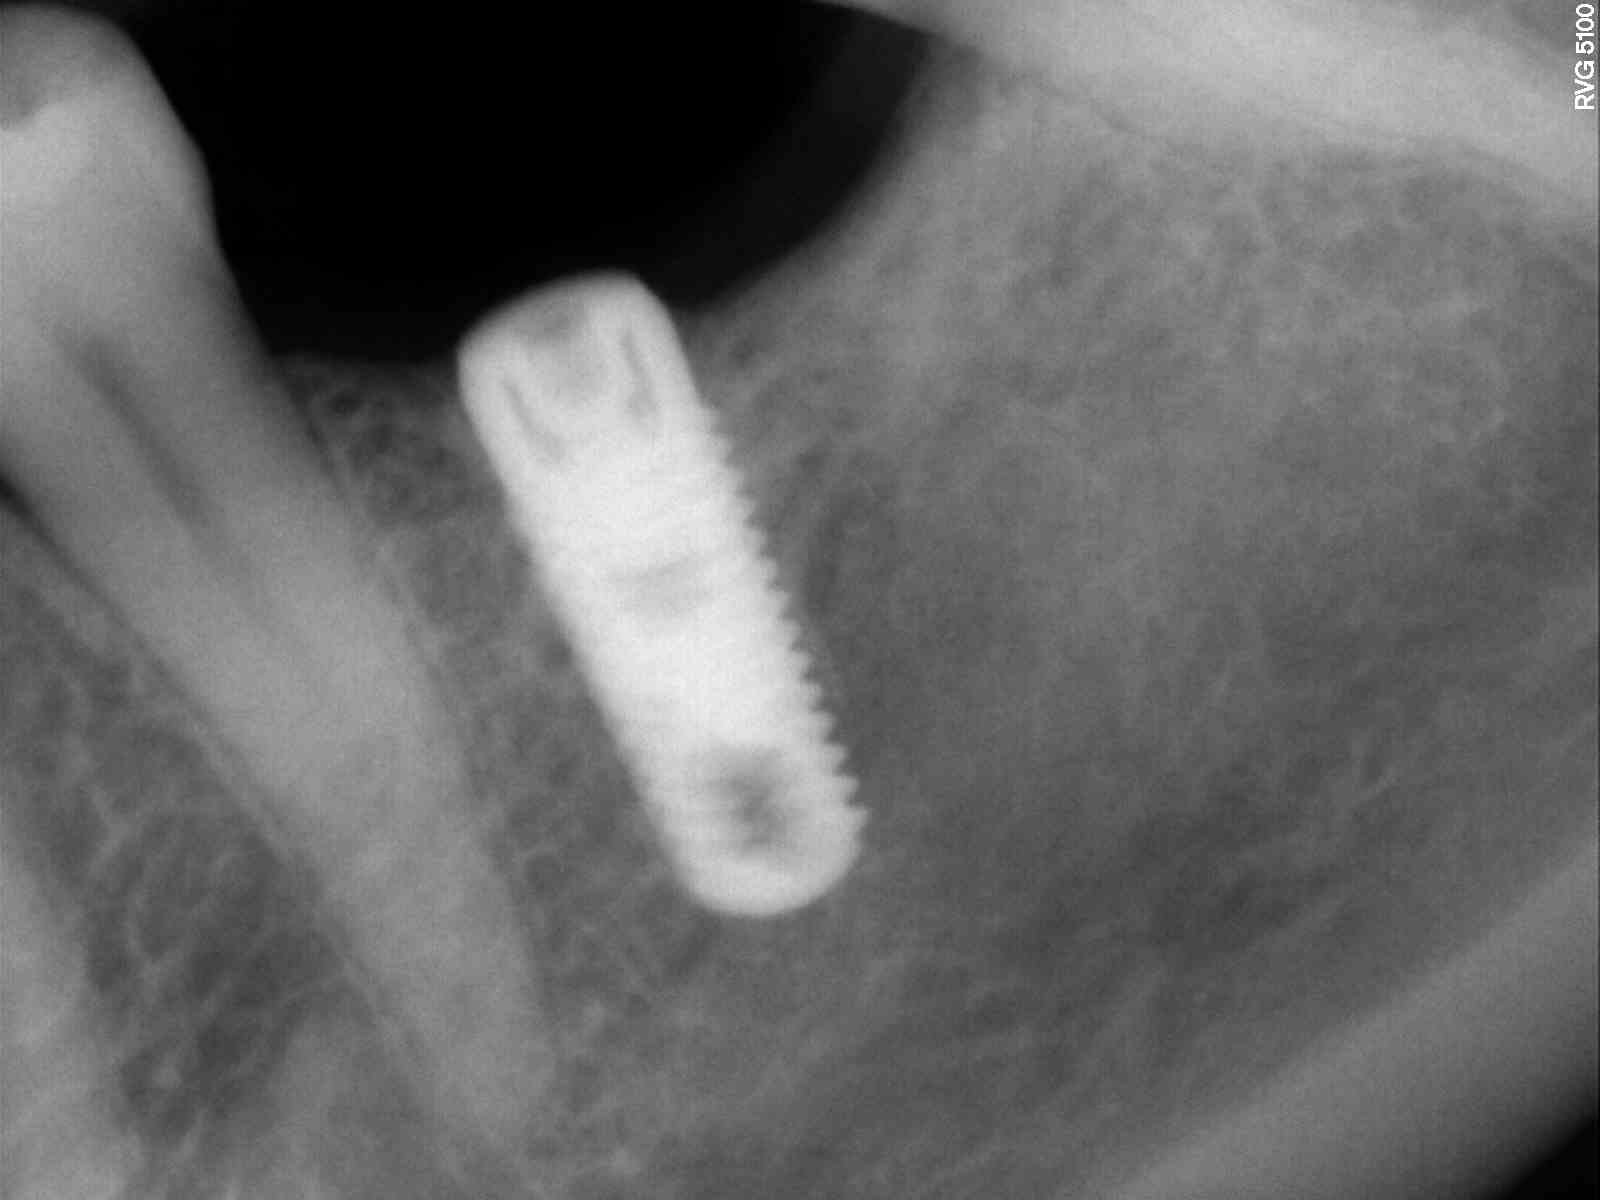

TENGO UNA PACIENTE CON UN IMPLANTE DE HACE AÑOS, QUE ES DE OTRA CONSULTA. NO PUEDE CONSEGUIR DE NINGUNA MANERA EL TIPO DE IMPLANTE QUE LLEVA. NECESITO SABER QUE TIPO [...]